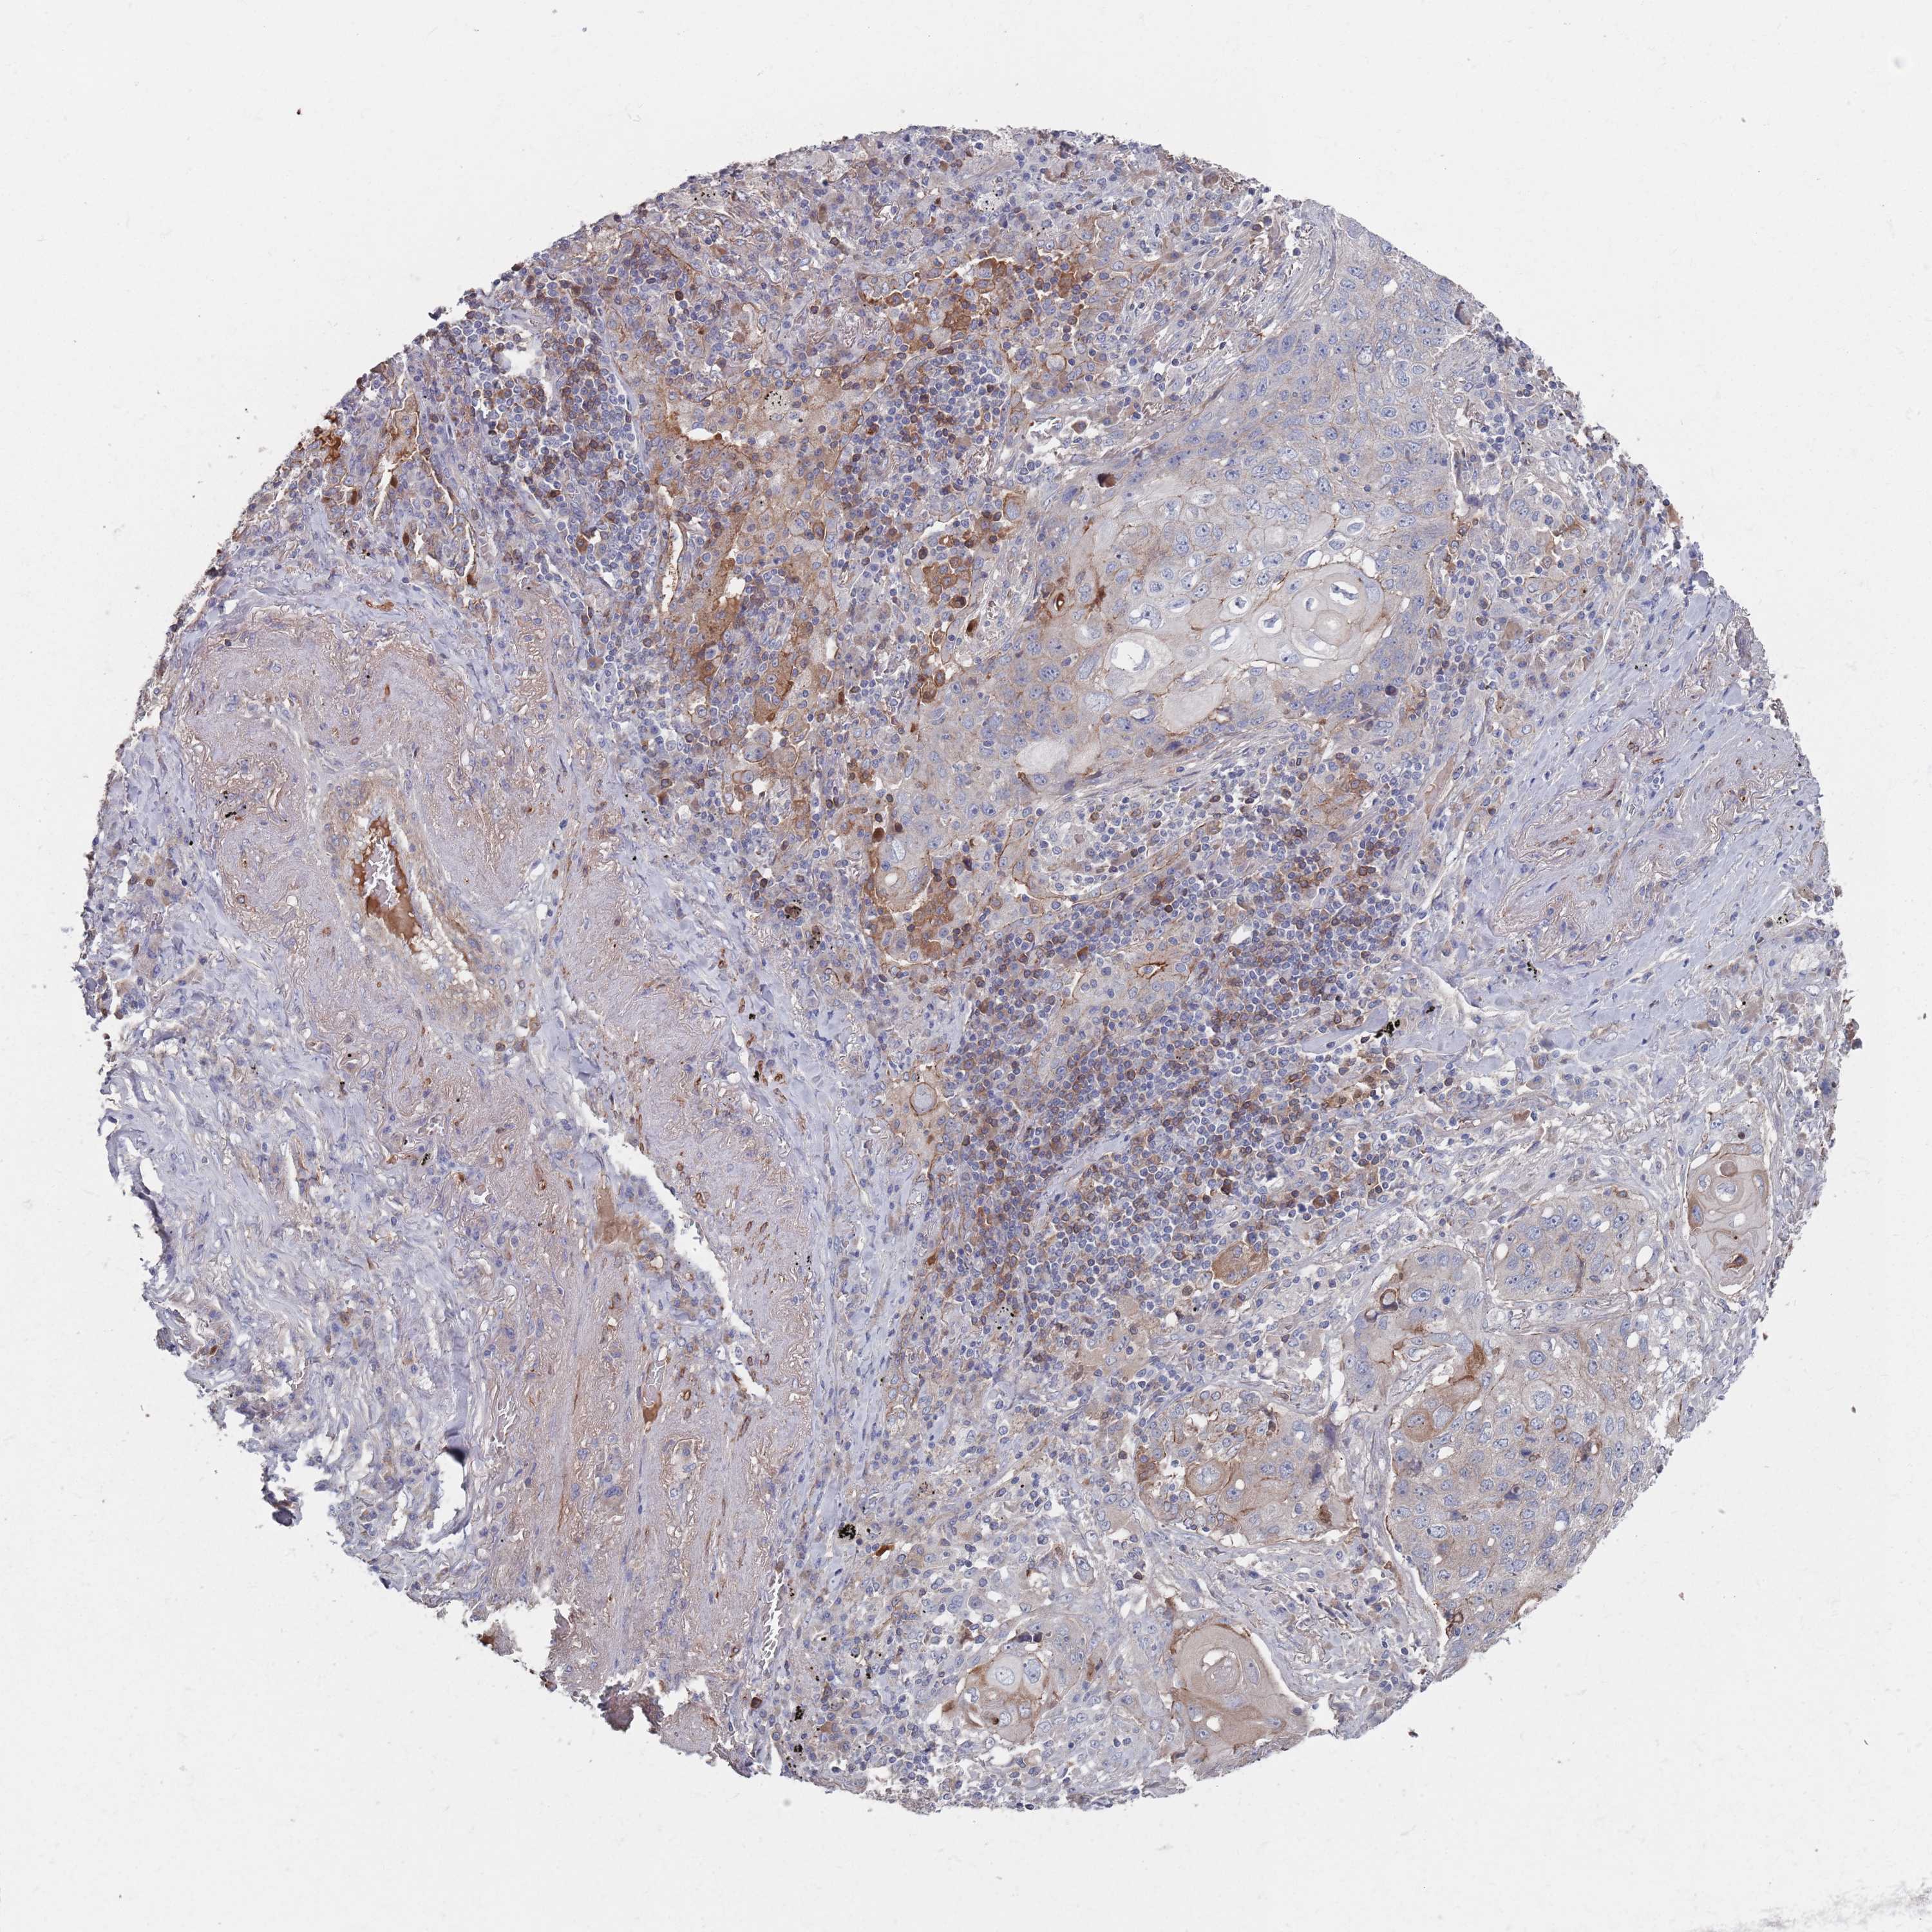

CANCER LUNG CANCER Show tissue menu

Lung cancer

Human cancer

Lung adenocarcinoma

Lung squamous cell carcinoma

PLEKHA4 is not prognostic in Lung Adenocarcinoma (TCGA)

: 7.34

Average pTPM 14.7

Number of samples 497

PLEKHA4 is not prognostic in Lung Adenocarcinoma (validation)

: 3.6

Average pTPM 6.4

Number of samples 105

PLEKHA4 is not prognostic in Lung Squamous Cell Carcinoma (TCGA)

: 9.09

Average pTPM 14.9

Number of samples 489